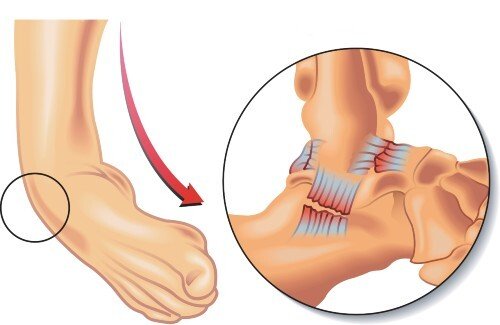

| Talipes | Deformity at the tarsal joint. | ![]() |